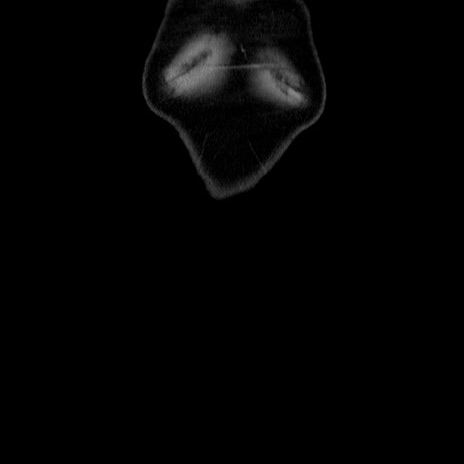

横断像

【症例】60歳代 男性

【主訴】右鼠径部膨隆

【現病歴】1年程前より右鼠径部膨隆あり。自己にて還納可能だったため放置していた。3時間前より右鼠径部の脱出を認め、還納困難となり受診。

【既往歴】高血圧

【身体所見】右鼠径部に小児頭大の膨隆あり。弾性硬であり、用手還納は困難。左鼠径部にも膨隆を認める。脱出はなし。